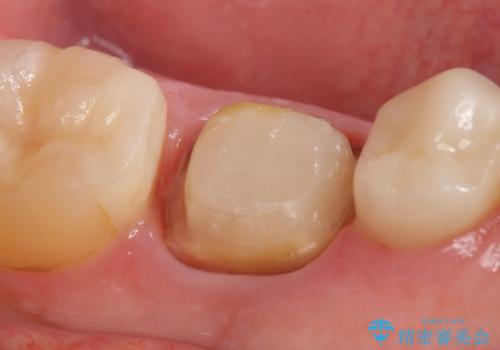

- 左下6番目の銀歯をオールセラミッククラウンにやり替えた症例です。

根管充填が不十分だったため再根管治療も行っております。

今回用いたオールセラミッククラウンはジルコニアフレームという白い素材の上にセラミックを盛っているため、審美性が非常に高いのが特徴です。